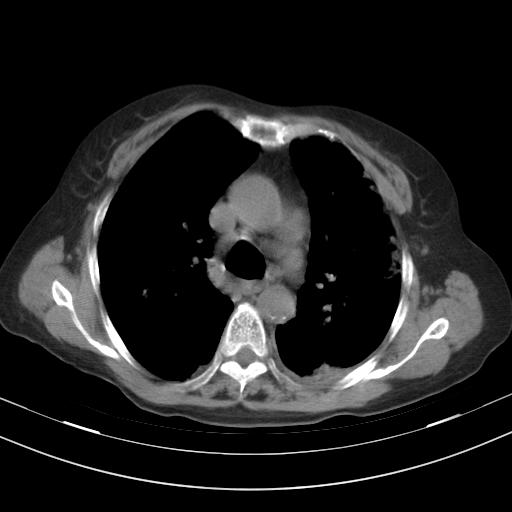

老年女性,嗜睡3天,意识模糊。轻咳,无发热。

1)两肺感染性病变;建议抗炎治疗后复查。2)纵隔淋巴结肿大。3)左侧胸腔积液。

1)先考虑两肺感染性病变;建议抗炎治疗后复查。

2)纵隔淋巴结肿大。

3)左侧胸腔积液。